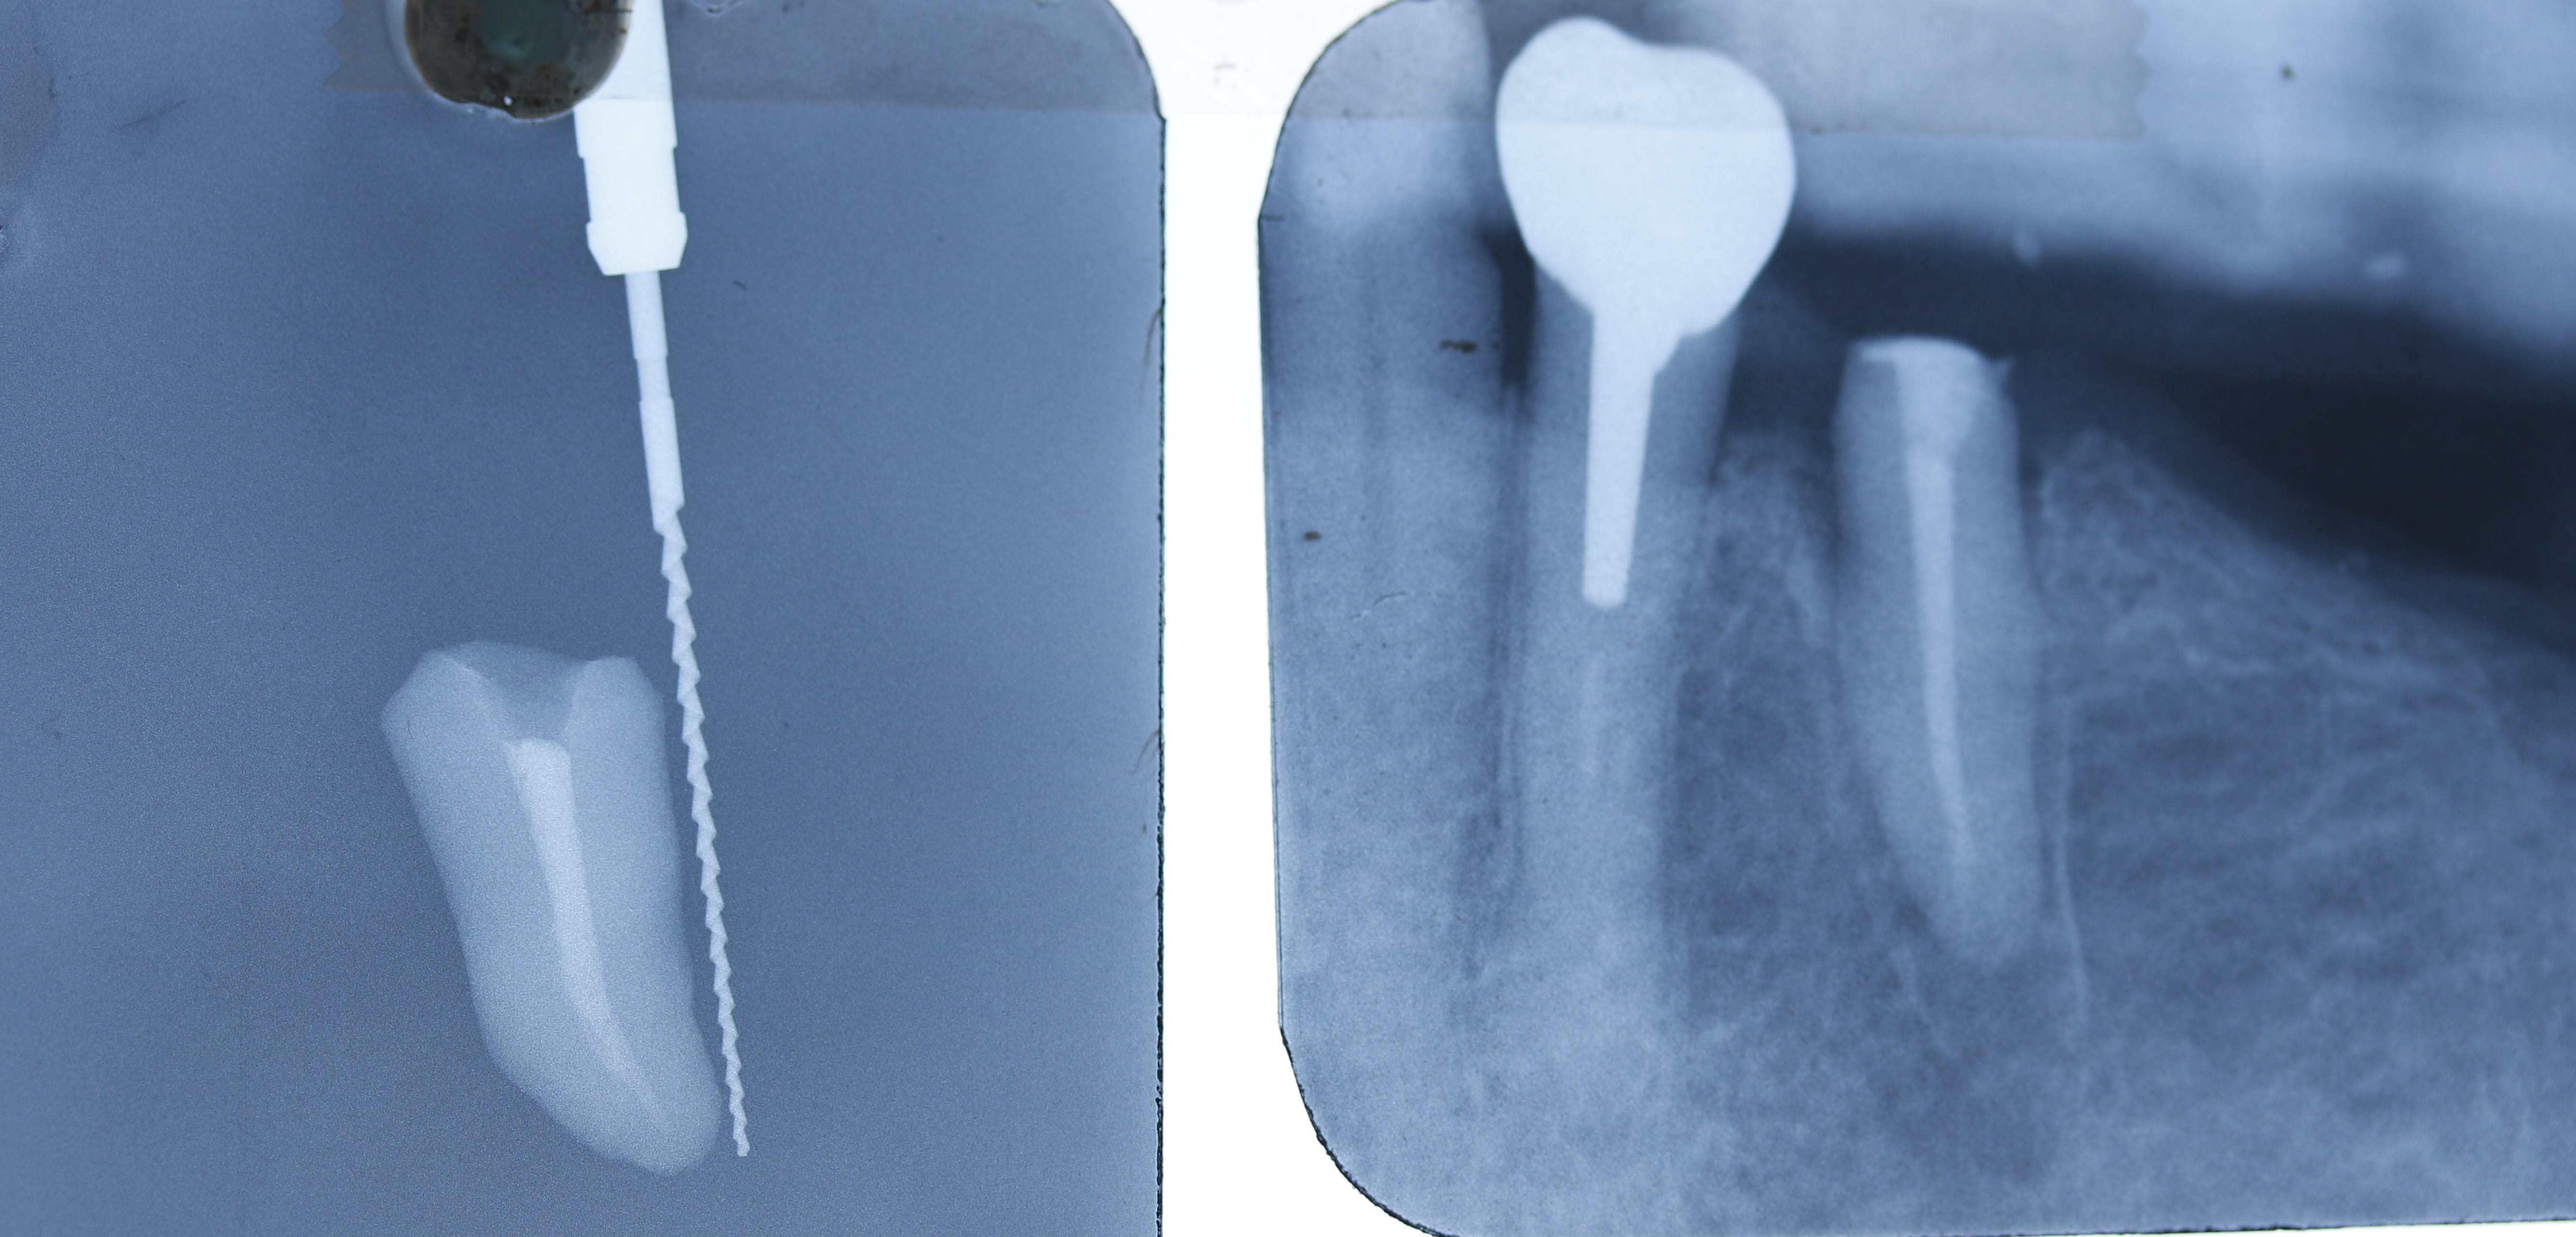

- Je vais pas virer ce genre de dent (voir photo et c’est une provisoire en place au passage désolé j’ai trouvé que ça je ne suis pas au cabinet)

-au delà de forcer l’espace biologique une limite profonde amène que des emmerdes difficulté de vérification de l’adapation, empreinte difficile même si comme me disent beaucoup de personne souvent un petit coup de fraise pour dégager la gencive et voilà tu la vois y’a limite ( ouais l’empreinte est pas mal mais je ne suis pas satisfait voir photo en distal c’est moyen et pas d’effet de ferrule en distal même minime)

Eh bien c est comme sur ta radio de la pm .

En mesial ton prov est au dessus de l ic . Impec .